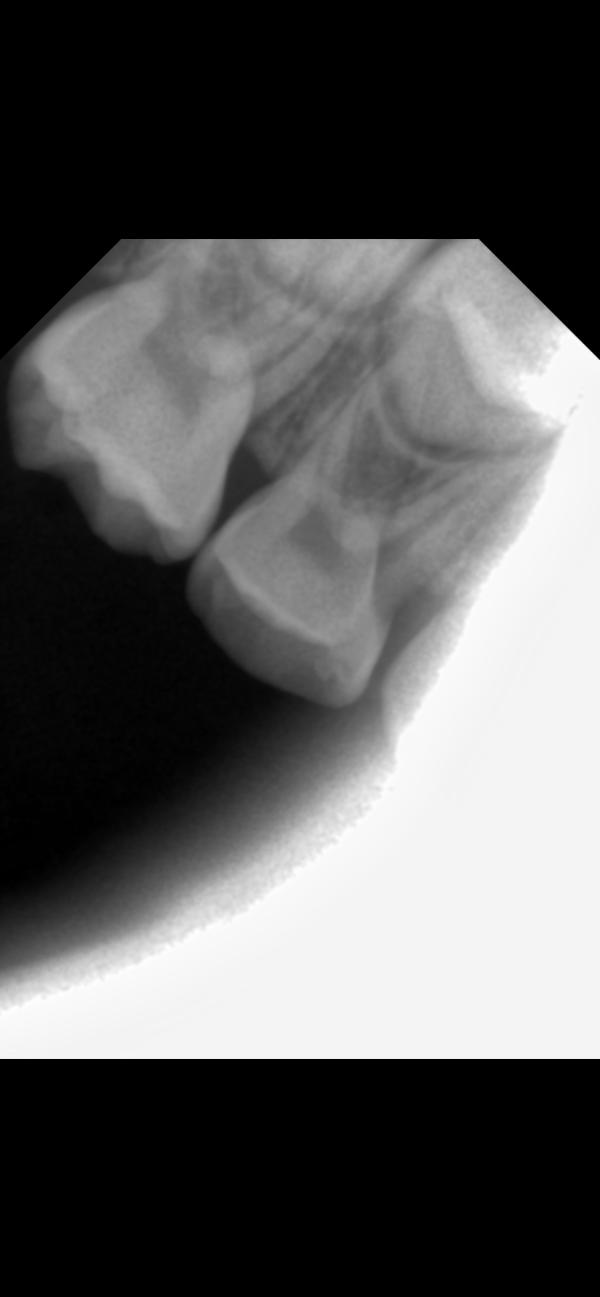

@isdarja, да, где затемнение на корне. У обоих единичек корни рассасываются уже, смысла их лечить никакого по сути нет. Но тот, что с воспалением, может повредить зачаток постоянного

Левую единицу удалять 100%. Остальные хорошо бы переделать снимки в другой проекции, не совсем понятно